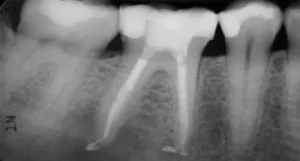

Root canal treatment is a common dental procedure designed to save a severely damaged or infected tooth. It involves removing the infected pulp, cleaning and

Root canal treatment is a common dental procedure aimed at saving a severely damaged or infected tooth. It involves removing the infected pulp, cleaning and